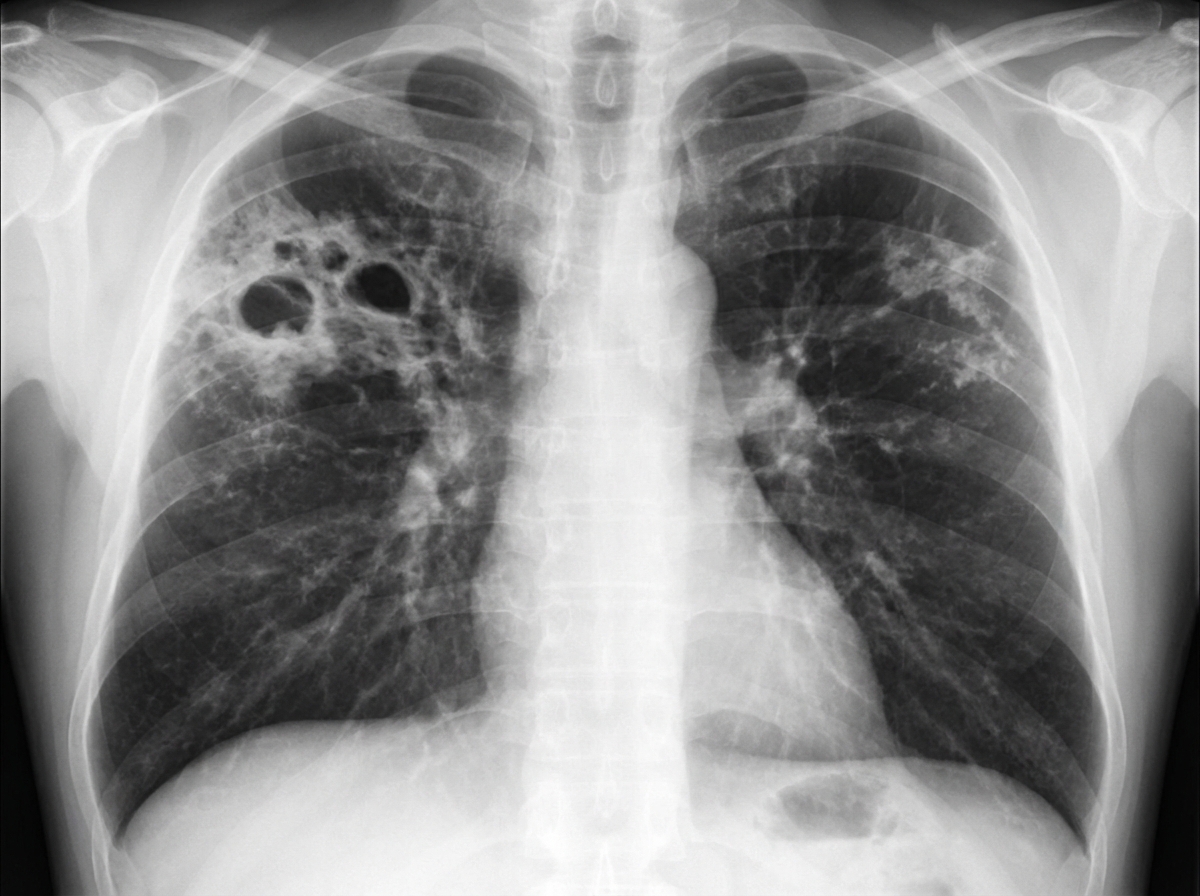

A 60-year-old man with a history of COPD and old TB presents with mild hemoptysis and chronic cough. He is HIV negative and has been ill for approximately 2 weeks. Vital signs: pulse 110 bpm; temperature 101°F; respirations 24/min; blood pressure 108/70 mm Hg. No skin lesions are noted. Laboratory data: Hb 14 g/dL; HCT 42%; WBCs 8.7/uL; BUN 24 mg/dL; creatinine 0.8 mg/dL; sodium 131 mEq/L; potassium 4.3 mEq/L. Arterial blood gases on room air: pH 7.37; PCO2 43 mm Hg; PO2 87 mm Hg. Sputum tests reveal numerous AFB-positive organisms on smear. Spirometry shows an obstructive ventilatory impairment with marginal reversibility. Chest X-ray is provided. Among the choices listed, what is the most likely diagnosis?

Explanation: ***Non-tuberculous mycobacteria*** - **AFB-positive organisms** on sputum smear in an **HIV-negative** patient with **COPD** and **prior TB** (damaged airways) strongly suggests **NTM pulmonary disease**. - Classic risk factors include **structural lung disease** from old TB and **COPD**, creating favorable conditions for **NTM colonization** and infection. *Lung abscess* - Would present with **purulent sputum** and **cavitary lesions** on chest imaging, but organisms would be **AFB-negative bacteria**. - Typically caused by **anaerobic bacteria** following aspiration, not **acid-fast organisms**. *Actinomycosis* - Caused by **Actinomyces israelii**, which is **not acid-fast** and would not show **AFB-positive organisms** on smear. - Characteristically produces **sulfur granules** in sputum and causes **chronic granulomatous infection** with chest wall involvement. *Aspiration pneumonia* - Usually involves **anaerobic bacteria** from oral flora, which are **AFB-negative** on microscopy. - Typically occurs in patients with **impaired consciousness** or **swallowing difficulties**, not necessarily associated with **AFB-positive organisms**.